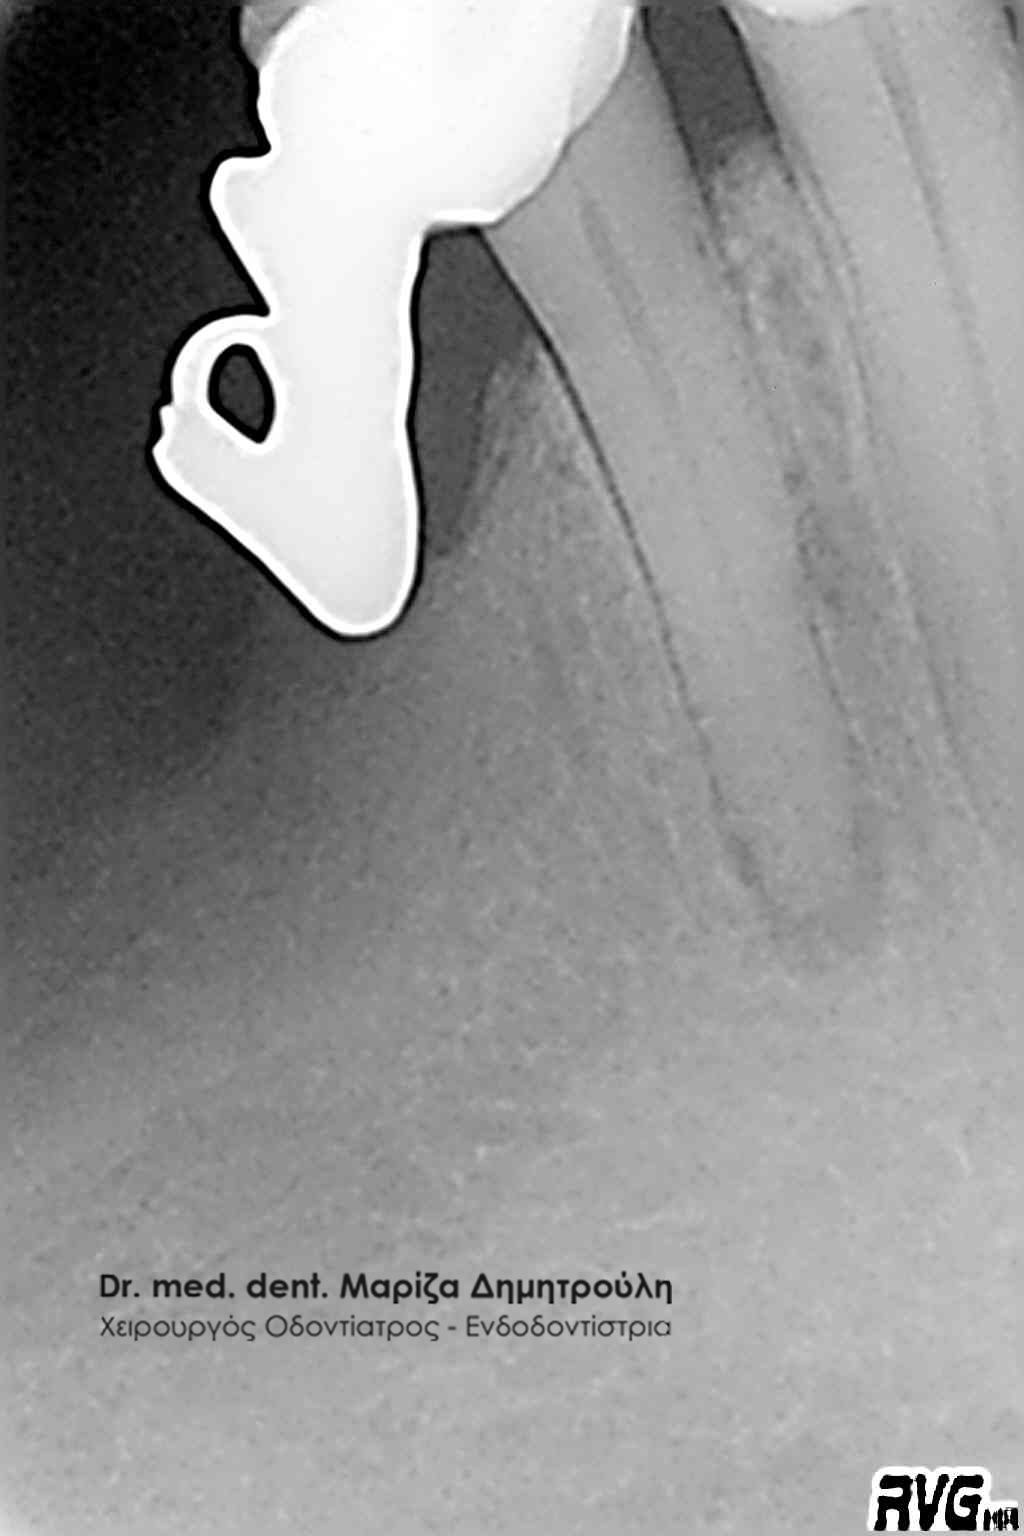

- με ενασβεστιωμένους ( κλειστούς ) ριζικούς σωλήνες

Οι ενδοδοντολόγοι είναι οδοντίατροι με περαιτέρω πανεπιστημιακή ειδίκευση, η οποία διαρκεί τουλάχιστον τρία χρόνια μετά την απόκτηση του πτυχίου του οδοντίατρου. Ο ενδοδοντιστής έχει ειδικευθεί στην απονεύρωση δοντιών με ασυνήθιστη μορφολογία, με στενούς ή έντονα κεκαμένους ριζικούς σωλήνες, κ.α., περιστατικά δηλαδή που συνήθως δεν μπορεί να αντιμετωπίσει ένας κοινός οδοντίατρος. Ο ενδοδοντιστής, σε σχέση με έναν κοινό οδοντίατρο, χρησιμοποιεί κατά τη διάρκεια της απονεύρωσης ειδικές τεχνικές, εξειδικευμένα εργαλεία και υλικά, αλλά και προηγμένο τεχνολογικό εξοπλισμό. Δεν είναι λίγες οι περιπτώσεις που ένας ενδοδοντολόγος έχει καταφέρει να “σώσει” δόντια, τα οποία από έναν κοινό οδοντίατρο είχαν καταδικαστεί σε εξαγωγή. Απαιτητικά περιστατικά για έναν ενδοδοντιστή χαρακτηρίζονται δόντια με ενασβεστιωμένους (κλειστούς) ριζικούς σωλήνες όπως και δόντια που απαιτούν επανάληψη ενδοδοντικής θεραπείας / απονεύρωσης (δόντια δηλαδή που είχαν ήδη απονευρωθεί στο παρελθόν και παρουσιάζουν εκ νέου φλεγμονή και ίσως αλλοίωση στο οστό).